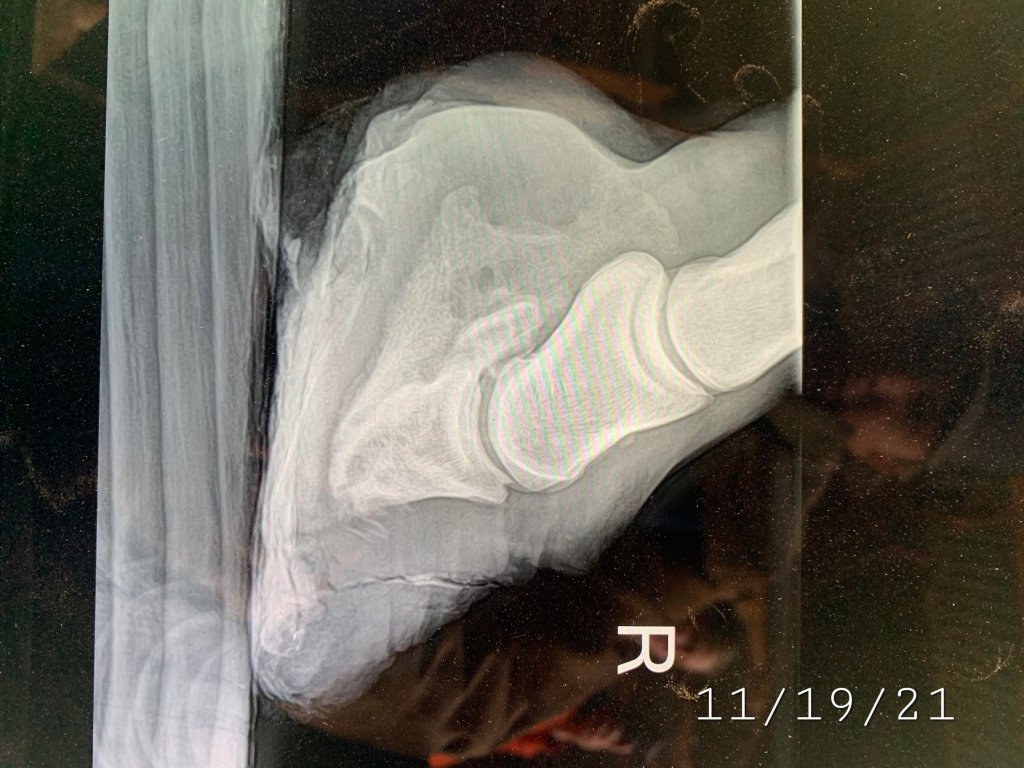

Revenge has Bi-Lateral Laminitis with Pedal Osteitis (demineralization of the coffin bone) she was also diagnosed with EPM, in treating the EPM she has started gaining growth weight quite rapidly and it’s putting an insane amount of pressure on her laminae (the glue that holds her foot together). This is causing her to sink further her sole is suppose to be about 15mm thick on her Right front it is maybe 2mm